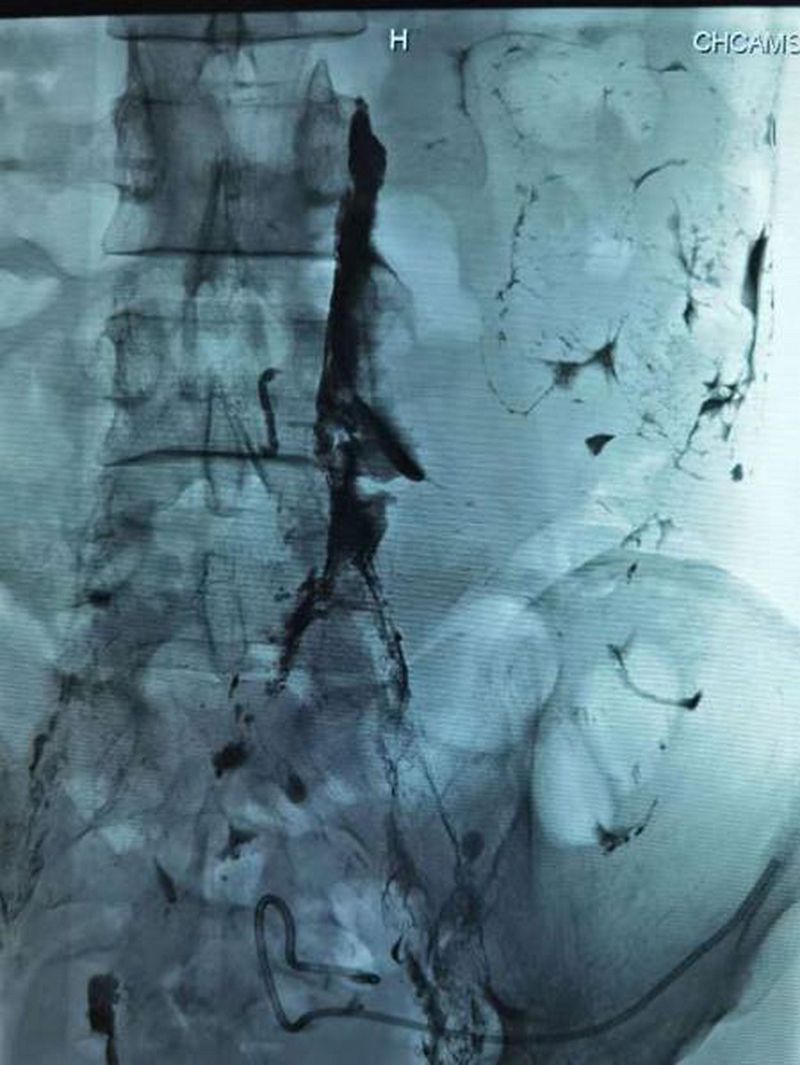

淋巴结造影找到破裂口(红色箭头 )

面对这样的情况,中国医学科学院肿瘤医院深圳医院立即组织开展多学科讨论,决定通过介入微创的方法来治疗顽固性淋巴漏。经过多学科充分的讨论与严谨的评估,介入治疗科副主任宋鹏为刘先生制定了严密的手术计划和诊疗方案——超声引导下穿刺腹股沟淋巴结,然后进行淋巴造影,造影确定漏口后进行淋巴漏的栓塞。

2021年6月9日,在介入治疗科副主任宋鹏和超声科医生的密切配合下,刘先生的左侧腹股沟淋巴结被告捷穿刺,连接注射器缓慢注射造影剂,通过每间隔3-5分钟摄影,大约1小时左右淋巴管破口也被顺利地找到。在宋鹏主任的精细操作下,一根纤纤细针穿过刘先生的腹腔,精准穿刺到漏口部位,随着微导管对缺口位置再次确认及生物胶的缓缓注入,淋巴管的破口被告捷封堵,手术取得了圆满告捷。